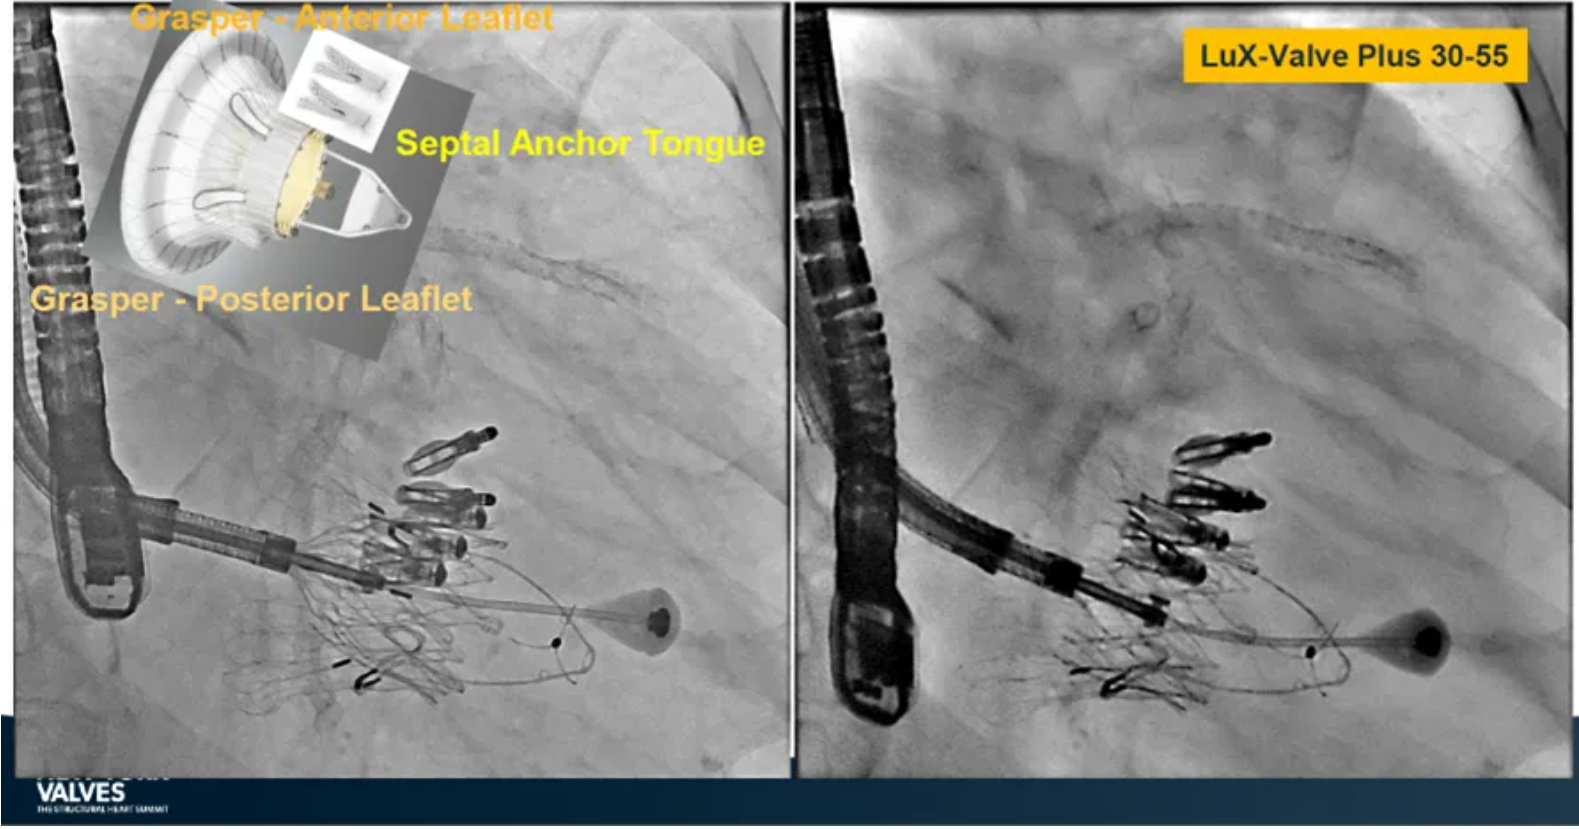

來自中國(guó)香港瑪麗醫(yī)院(Queen Mary Hospital, Hong Kong, China)的Simon Lam教授在2024紐約瓣膜會(huì)上分享了一例復(fù)雜案例,一名高齡男性患者在2年前行二尖瓣和三尖瓣TEER術(shù)式后繼發(fā)三尖瓣反流,遂再次行二尖瓣TEER術(shù)式和用LuX-Valve Plus行三尖瓣TTVR術(shù)式。

本次術(shù)式中,LuX-Valve Plus的植入緊隨二尖瓣修復(fù)術(shù)式之后,且并未取出前期植入的三尖瓣修復(fù)夾,這意味著LuX-Valve Plus在患者有過二尖瓣和三尖瓣修復(fù)夾植入情況下的兼容性,并且?guī)砹擞行У闹委熃Y(jié)果。此外,這不僅體現(xiàn)了LuX-Valve Plus可以與二尖瓣術(shù)式并行,更可以兼容三尖瓣原位的其他修復(fù)夾產(chǎn)品。